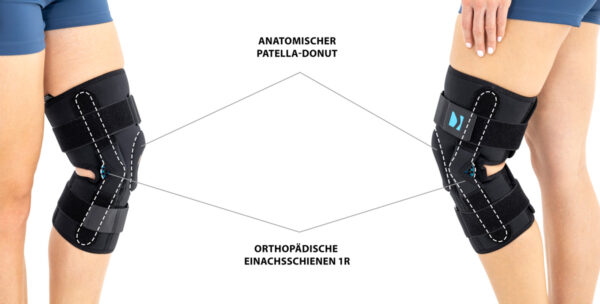

ANATOMICZNY PIERŚCIEŃ OKOŁORZEPKOWY

TYLNA OTWARTA ORTEZA STAWU KOLANOWEGO Z REGULACJĄ ZAKRESU RUCHOMOŚCI CO 15 STOPNI

Konstrukcja ortezy jest projektem unikatowym, łączącym w sobie zarówno fukcję ortez otwartych – łatwość zakładania wyrobu poprzez brak konieczności wciągania ortezy przez stopę, jak również zamkniętych – pełna stabilizacja rzepki i stawu kolanowego. W tym celu w wyrobie zainstalowano anatomicznie ukształtowany pierścień rzepki.

Konstrukcja ortezy jest projektem unikatowym, łączącym w sobie zarówno fukcję ortez otwartych – łatwość zakładania wyrobu poprzez brak konieczności wciągania ortezy przez stopę, jak również zamkniętych – pełna stabilizacja rzepki i stawu kolanowego. W tym celu w wyrobie zainstalowano anatomicznie ukształtowany pierścień rzepki.

2in1 SOLUTION to unikatowy projekt łączący w sobie zarówno funkcje ortez otwartych – łatwość zakładania wyrobu poprzez brak konieczności wciągania ortezy przez stopę, jak również zamkniętych – perfekcyjna stabilizacja rzepki oraz stawu kolanowego. W tym celu wyroby te zostały wyposażone w anatomicznie ukształtowany pierścień rzepki. Dodatkowym atutem jest unikatowy design ortez, który zawiera otwarty dół podkolanowy, co dodatkowo zwiększa komfort ich użytkowania. Takie rozwiązanie pozwala na odprowadzanie potu od kończyny, co pozwala na swobodne i nieuciążliwe stosowanie ortezy.